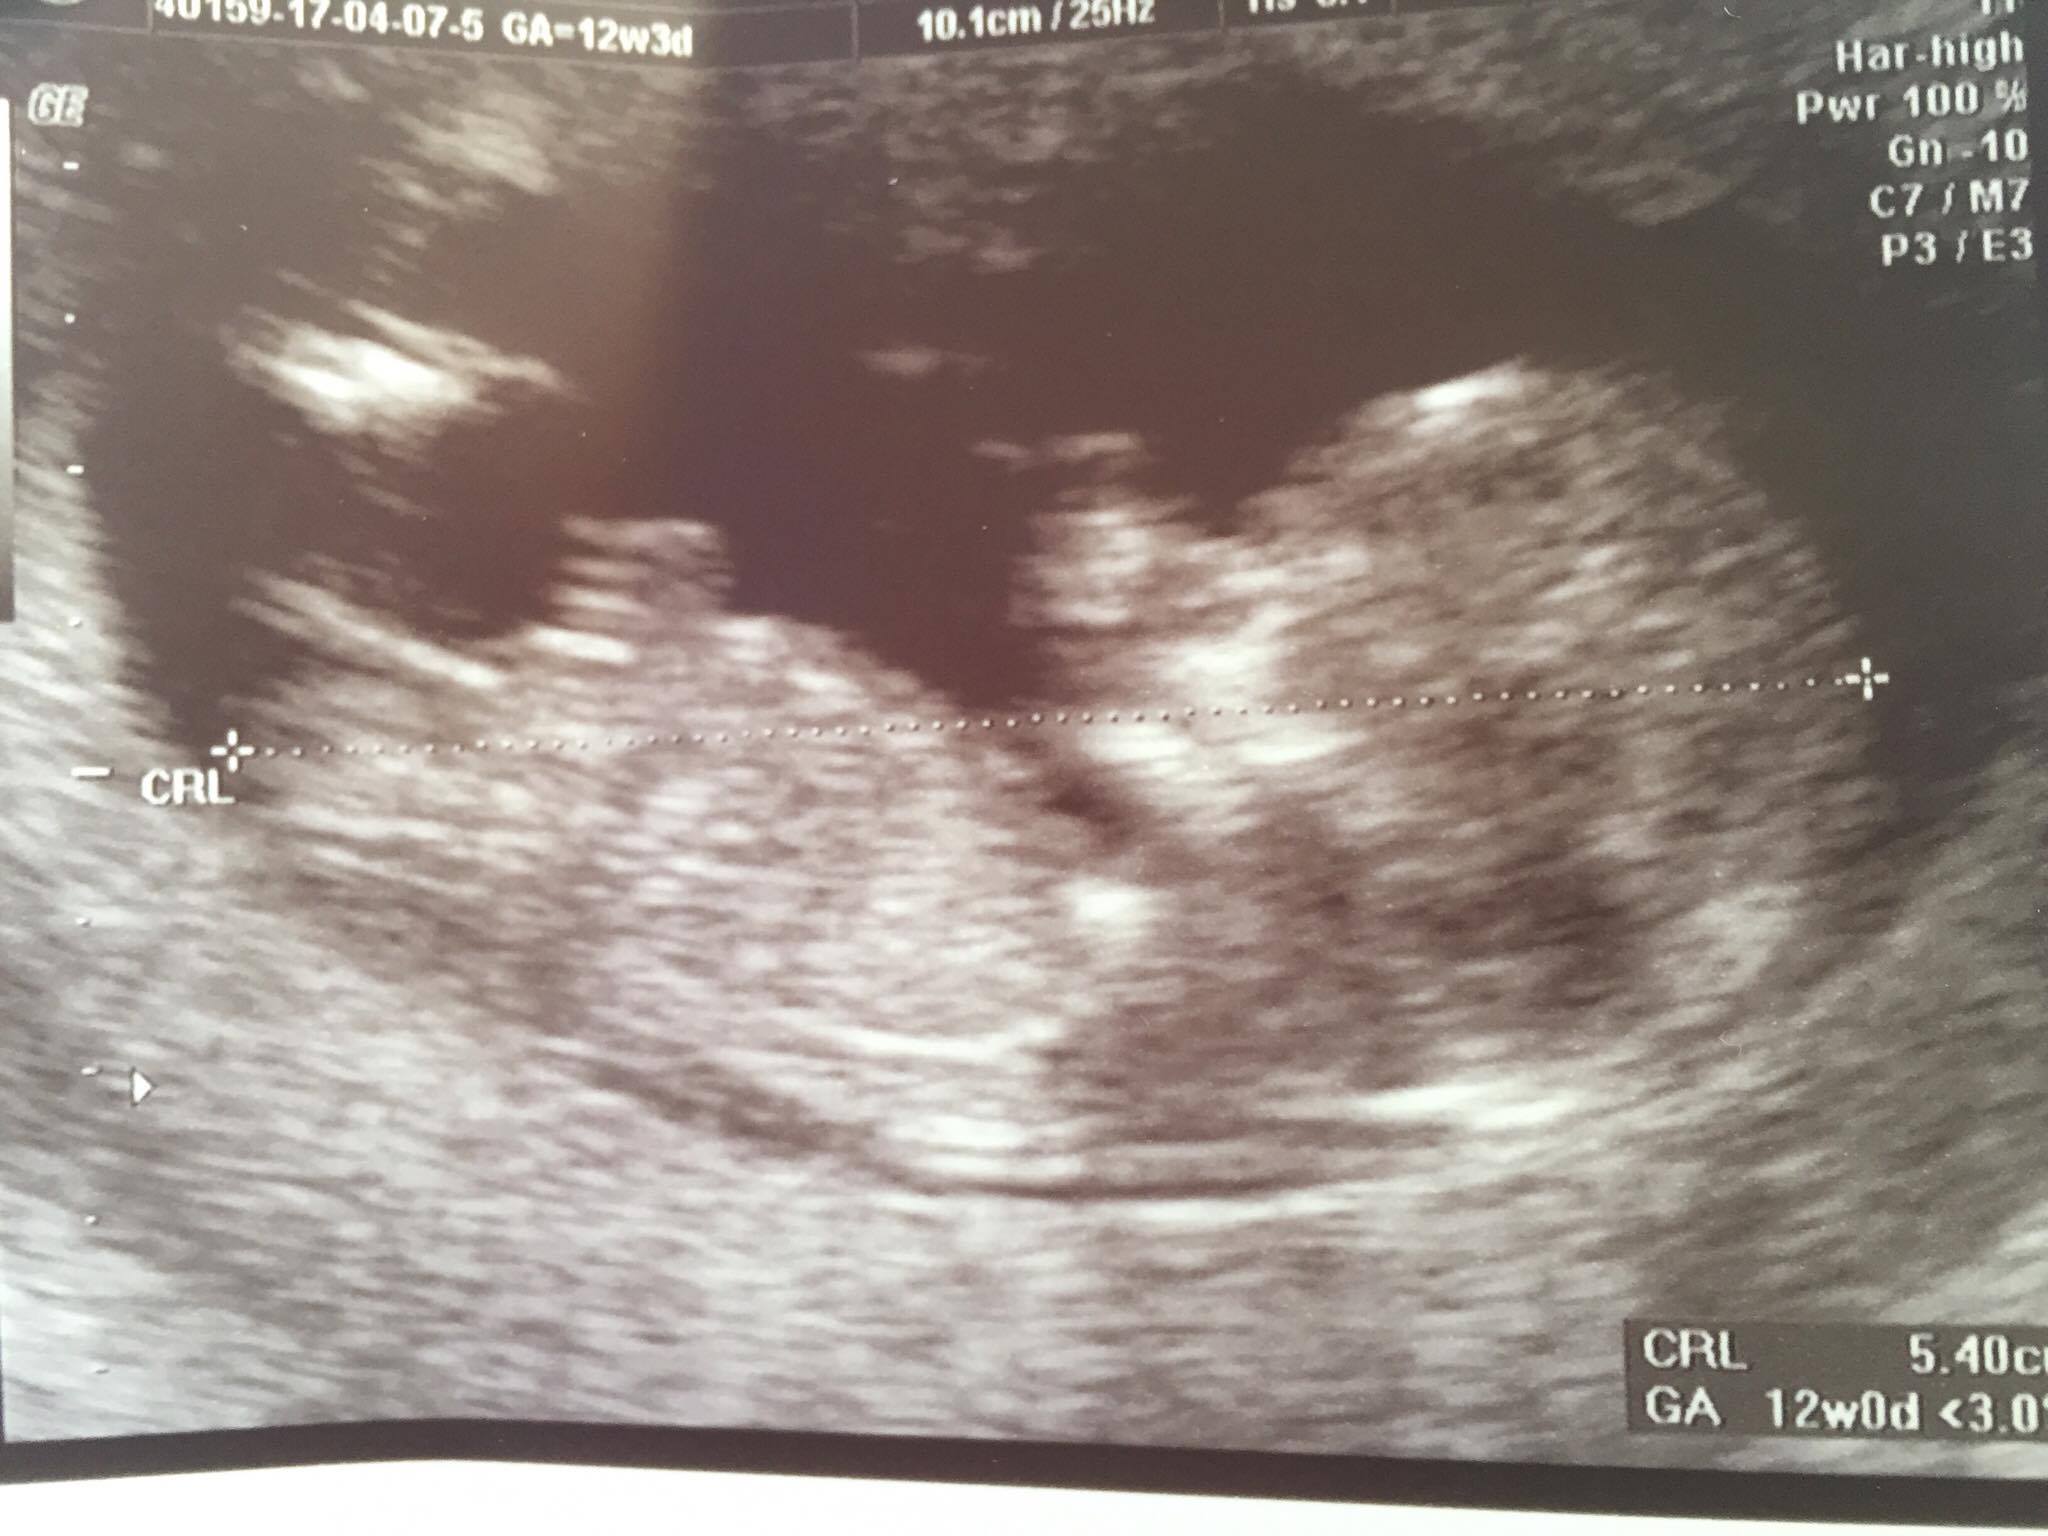

Attachment 35934Attachment 35934

12w.. boy or girl ? What do you think, girls? :)

Boy for both x

Thanks :) The doctor said that 90% for a girl ;)